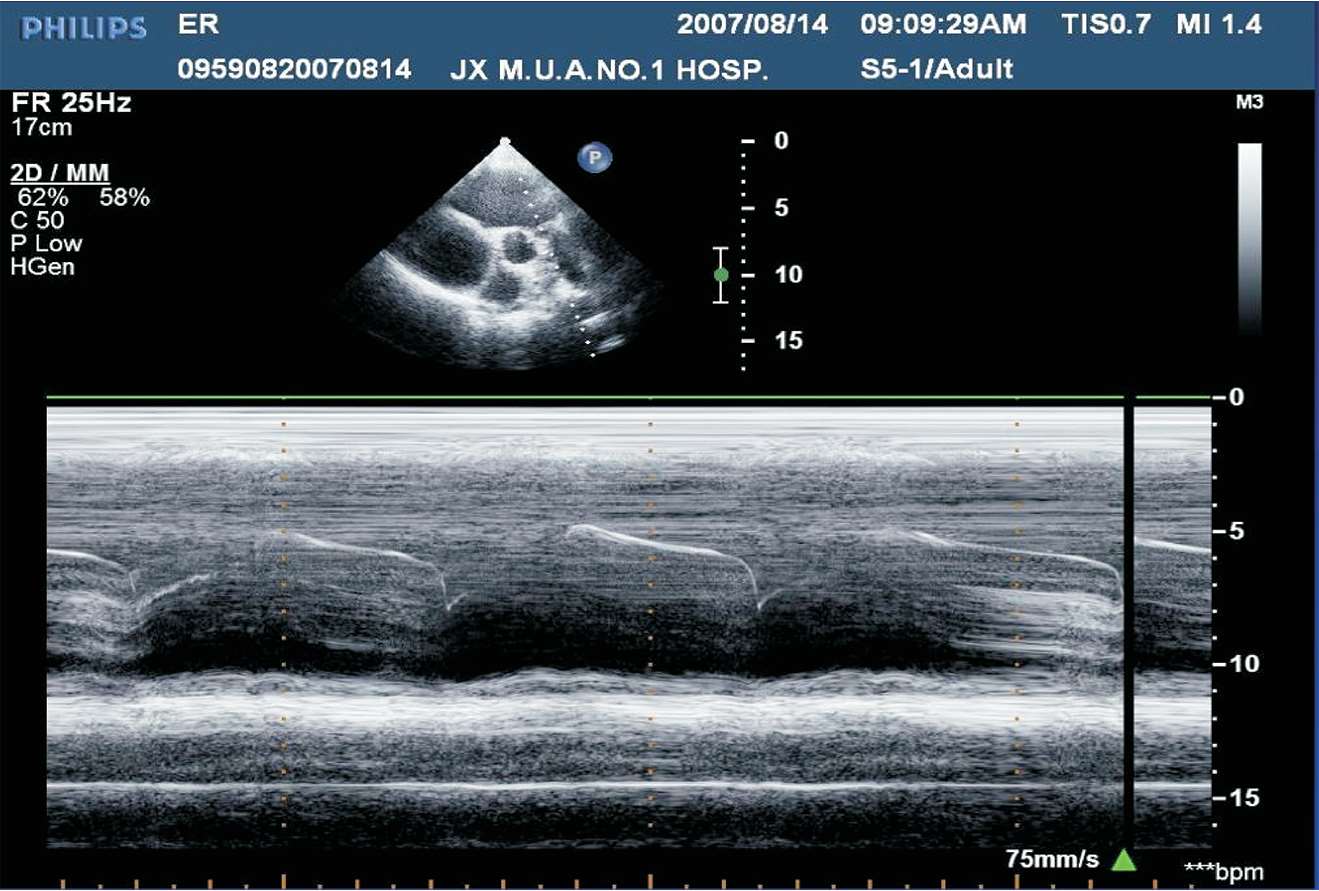

M型超声心动图在二维成像基础上通过不同取样线,以时间为横轴,获得取样线上心脏组织结构随时间变化产生的运动频谱。常见波形有心底波群、二尖瓣波群、心室波群、肺动脉瓣波群。

(1)胸骨旁左室长轴切面M型取样线置于主动脉瓣瓣尖水平。

(2)结构从前到后依次为右室流出道、主动脉、左心房等。其中右室流出道及主动脉根部内径于舒张末期测量,左心房前后径于收缩末期测量(见图1-21)。

图1-21 心底波群(RV:右心室;AO:主动脉;LA:左心房)